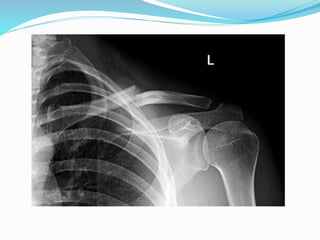

El documento trata sobre la anatomía y la funcionalidad del complejo articular del hombro, enfocándose en espacios quirúrgicos específicos en la región posterior. Se presenta información relevante sobre la cintura escapular y su relación con el hombro. El análisis realizado por el Dr. Luis Francisco Chávez Flor abarca aspectos clave para la comprensión de procedimientos quirúrgicos en esta área.